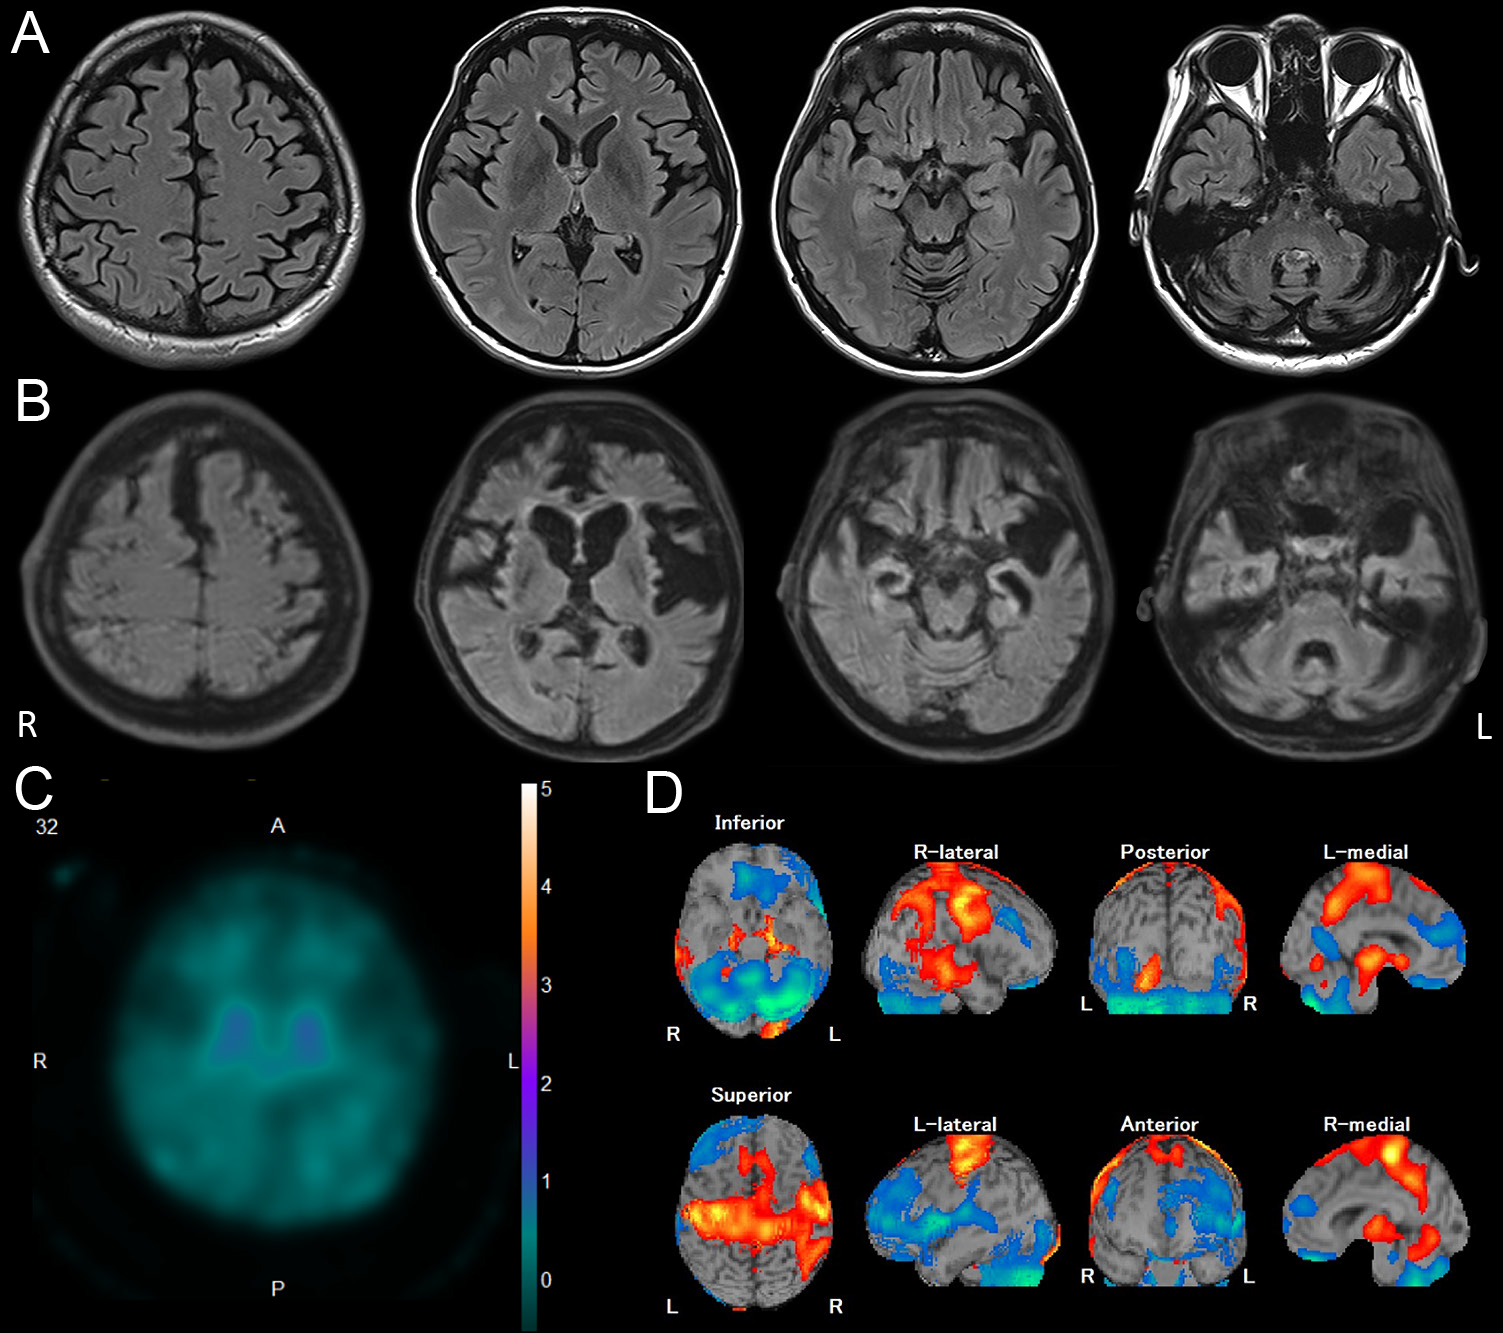

小児期に発症し49歳までの長期経過を観察し得たホスホリパーゼA2group6関連神経変性疾患女性例

A female case of phospholipase A2 group VI-associated neurodegeneration with childhood onset and long-term follow-up until 49 years of age

三森 雅広, 金澤 恭子, 佐藤 和貴郎, 雑賀 玲子, 弓削田 晃弘, 瀧山 嘉久, 髙橋 祐二

Masahiro Mimori, Kyoko Kanazawa, Wakiro Sato, Reiko Saika, Akihiro Yugeta, Yoshihisa Takiyama, Yuji Takahashi

2026/03/11